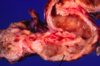

What is this?

- Ulcerative colitis: isolated islands of regenerating mucosa often bulge into the lumen to create PSEUDOPOLYPS

- Biopsy is going to be much smaller than the image shown here (and more superficial)